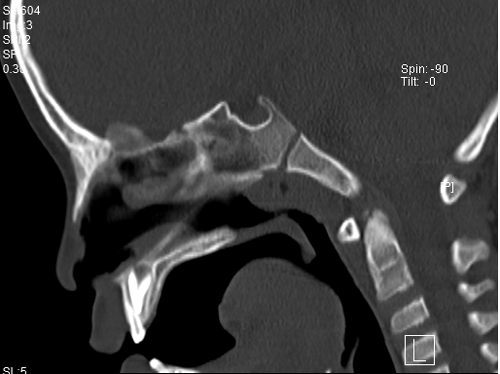

耳鼻咽喉科主任胡少爭(zhēng)

對(duì)慶慶仔細(xì)進(jìn)行

耳鏡和鼻鏡等相關(guān)檢查

除了已經(jīng)形成典型的

腺樣體面容以外

腺樣體肥大

已占據(jù)鼻咽部空間約80%

同時(shí)發(fā)現(xiàn)鼓室內(nèi)有積液

慶慶進(jìn)行了全麻下行

鼻內(nèi)鏡低溫等離子

腺樣體切除微創(chuàng)手術(shù)